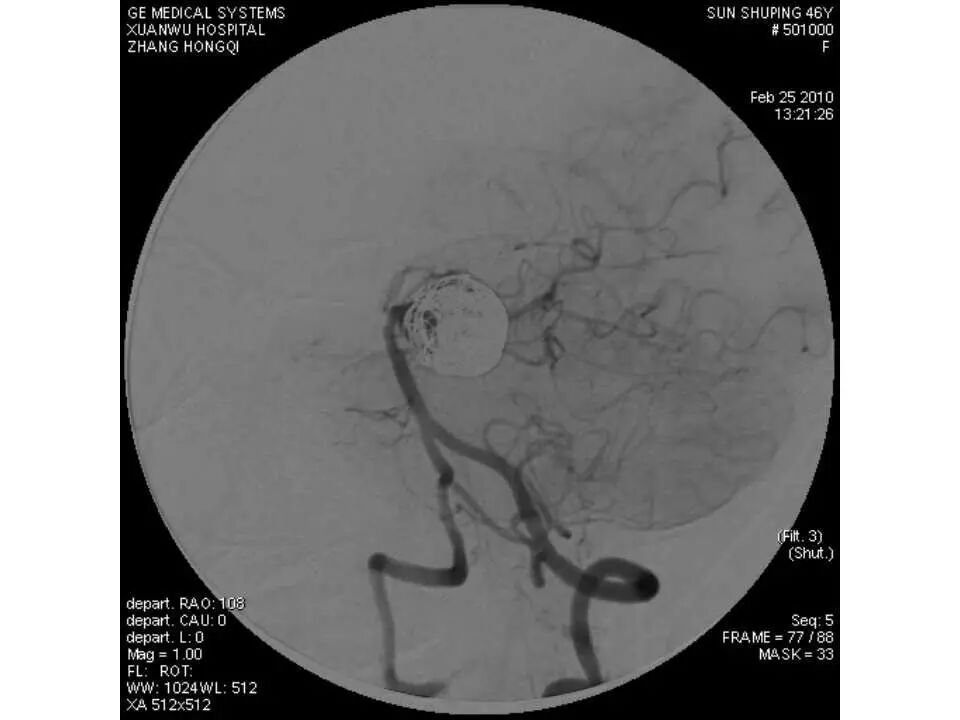

今天为大家分享的是“强生医疗CNV-神经介入专栏”第十五期,由首都医科大学宣武医院何川教授带来的“颅内动脉瘤介入治疗”精彩讲课视频及PPT,欢迎观看、阅读。文章仅代表作者个人观点,如有不同见解,欢迎同道斧正!

何川 ,首都医科大学宣武医院副主任医师,中国医师协会神经介入专业委员会常务委员,长期从事脑血管病和脊髓血管病的手术及介入治疗和相关研究工作。首都医科大学神经外科博士,师从于中国神经介入开创人凌锋教授;日本东北大学医院脑血管病治疗科博士后,师从于日本国脑血管病血管内治疗的开创者高桥教授。